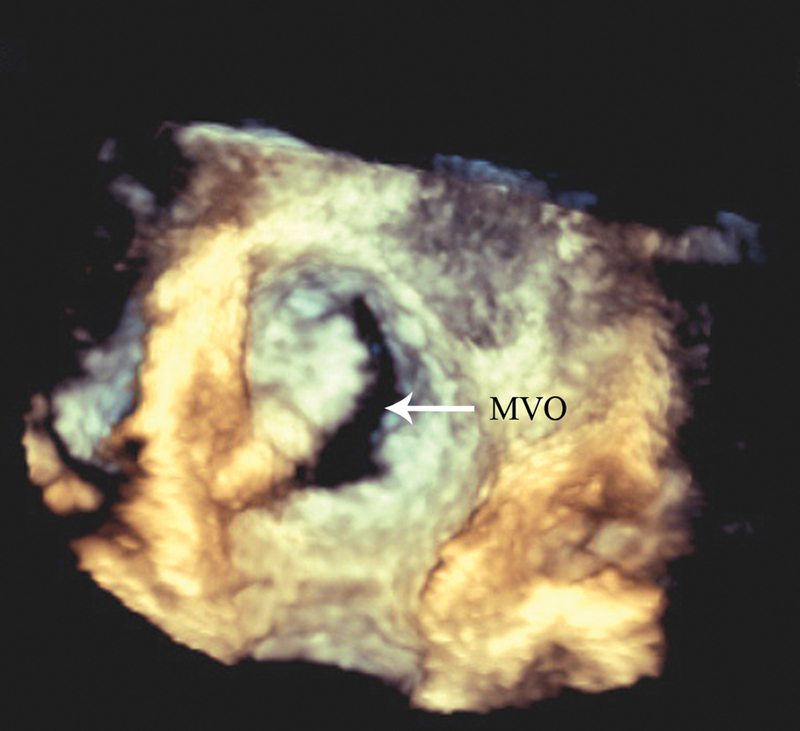

فحوصات تشخيصية لبعض امراض القلب والشرايين التاجية